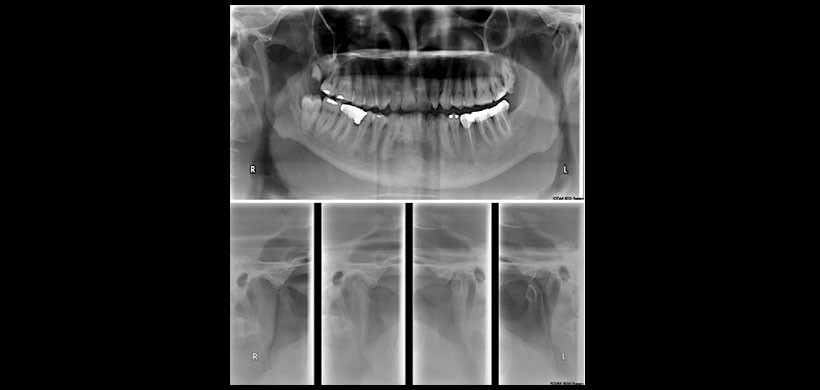

Fig 3.Radiografía panorámica y de ATM de un paciente masculino de 50 años quien manifestó dolor preauricular en el lado derecho e izquierdo desde hace 1 año, el dolor se agrava a los movimientos de rotación del cuello. La radiografía panorámica muestra una mineralización elongada de los procesos estilohiodeos de aproximadamente 65 y 60 mm respectivamente.